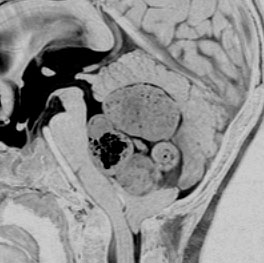

この例は,小脳半球にできたものです。のう胞(水たまり)を形成しています。髄芽腫の大きな特徴は,造影剤を入れないCT(左側)で腫瘍が少し白く見えることです(灰白質より高密度といいます)。細胞密度が高いので高密度になります。この例はclassic medulloblastomaですが,MIB-1は45%に達するもので,急激な腫瘍発育を示します。